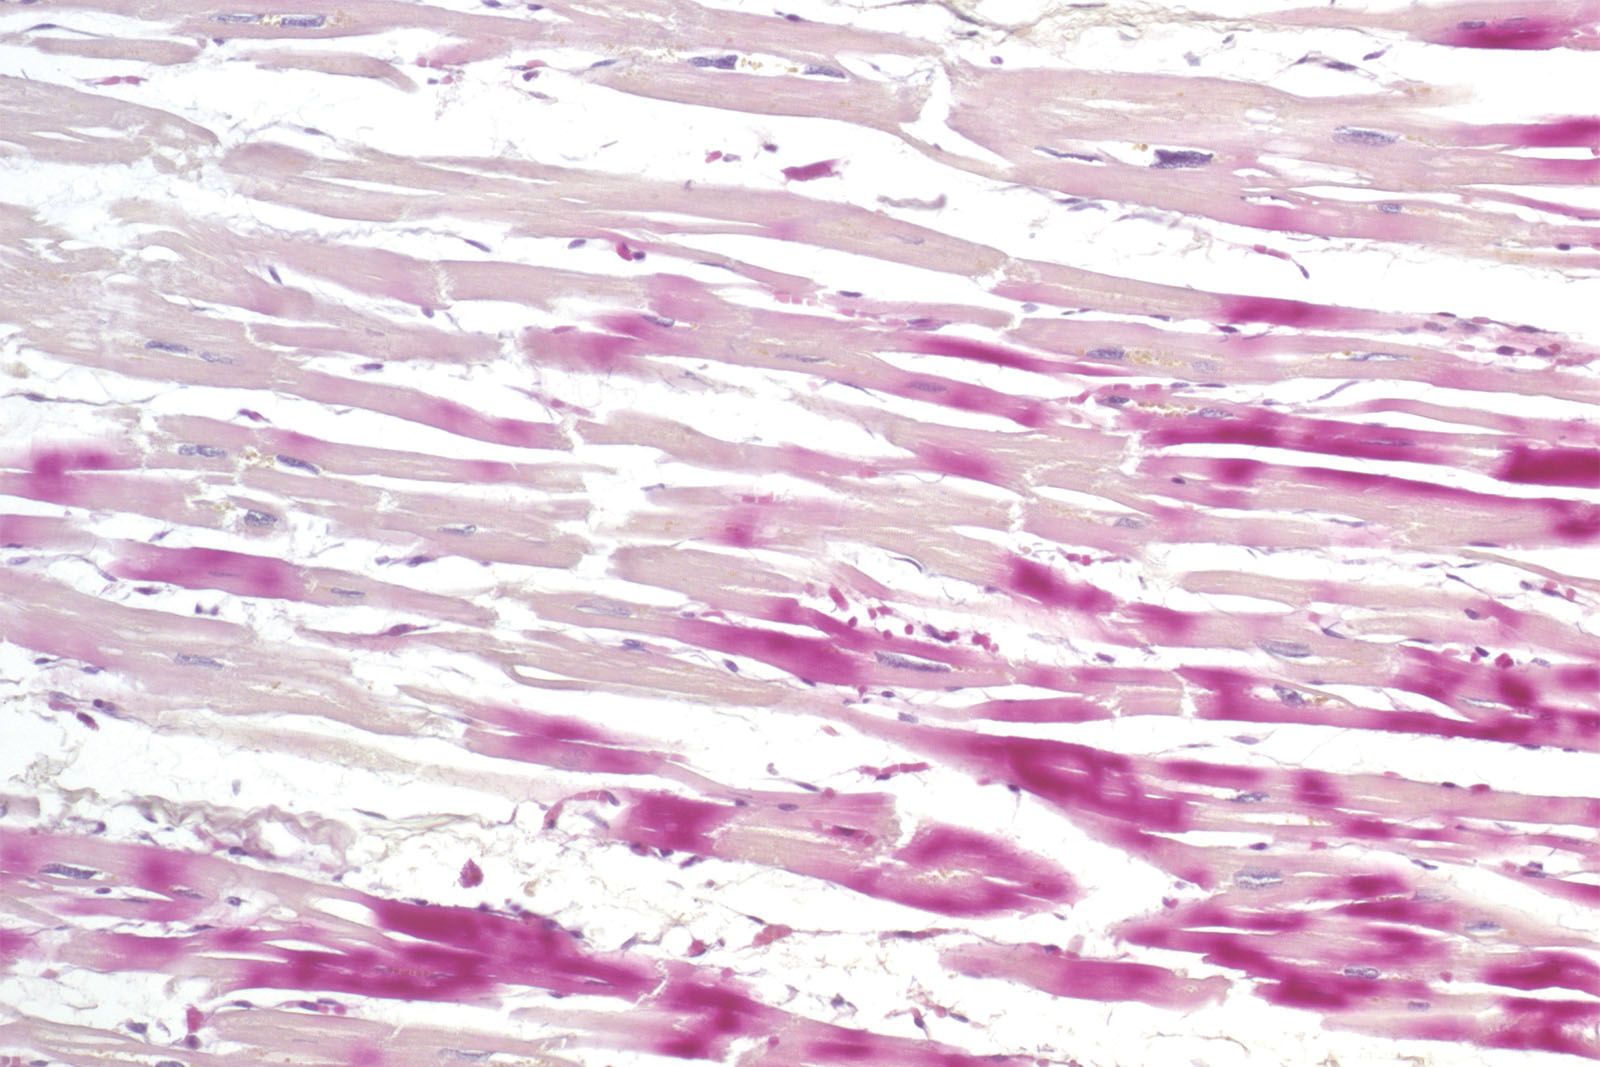

Histological diagnosis of ischemia in the early phase of myocardial infarction using the standard hematoxylin-eosin histological methods and a light microscope is exceptionally delicate. The reason for that is minimal histopathological changes occurring on the cardiac muscle during the first six hours of symptoms. However, staining the section using the kit consisting of hematoxylin, basic fuchsin and picric acid enables a histological overview of early changes on the cardiac muscle caused by ischemia or myocardial infarction.